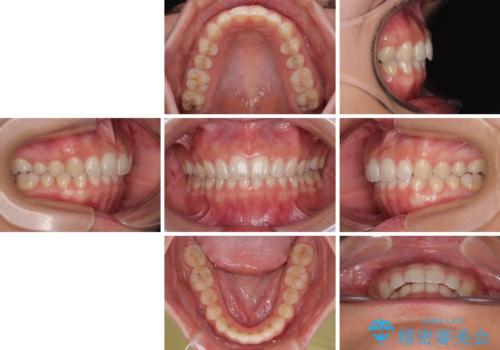

- 上の前歯が前方に飛び出していることを気にして来院された患者様です。

奥歯の咬み合わせをチェックすると、上顎歯列が相対的に前方に位置しているため、補助装置を用いて上顎歯列を確実に後方に移動させ、インビザラインで歯列を整えて行くこととしました。

インビザライン単体でも同様の結果が得られる可能性がありますが、万が一奥歯がうまく後方移動できなかった場合、リカバリーが非常に大変となるため、事前に補助装置を併用して確実に結果が得られるように工夫をしています。